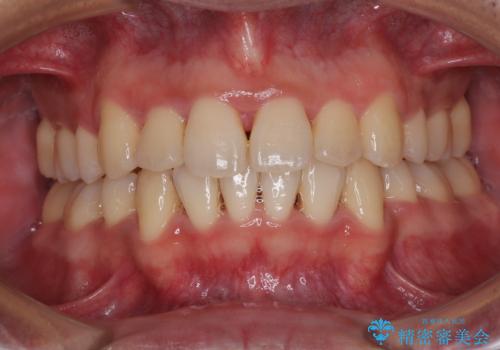

色のバランスの悪い前歯 オールセラミッククラウンで自然な口元に